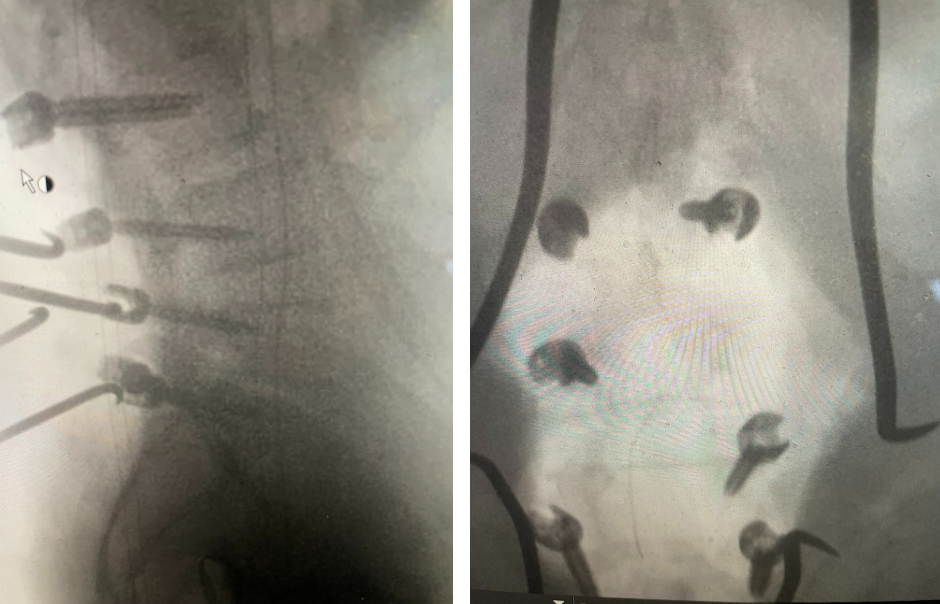

Figure 3. AP and lateral intraoperative fluoroscopic images demonstrating balanced pedicle screw placement.

We decided to perform a lumbar decompression L2-S1 with an instrumented fusion. The patient intraoperatively had severe thecal sac compression with severe facet arthropathy and thickened ligamentum flavum. The patient had bilateral L5 pars defects with a floating L5 lamina. Because of these factors and the patient’s age, it was decided to place screws (Fig. 3). The patient did well postoperatively with relief of his lower extremity pain and weakness.